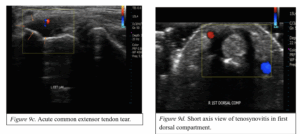

A focussed hand specific clinic assessment (table 4) can help to rule in or out complete ruptures but is less sensitive for (partial tears). Where a closed tendon rupture is suspected and the clinical exam is uncertain, imaging can help to confirm a diagnosis. MRI is the gold standard imaging for closed tendon injuries and has good sensitivity, but US is generally preferred as it allows the benefit of dynamic assessment of tendons, locating retracted tendon ends and more chronic conditions, such as tendinopathy or tendinosis (Figure 1-2).

Figure 9. Ultrasound images of various tendinous pathologies.